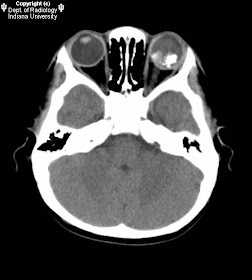

Findings

Large calcified mass in the left lobe optic globe posteriorly in contact with the optic nerve. Left optic globe size near symmetric with the right.

Diagnosis: Retinoblastoma

CT demonstrates a solid retrolental hyperdense mass with associated retinal detachment. Associated findings include extraocular extension, optic nerve enlargement, and partial or complete calcification. Calcification is commonly seen and is a good prognostic indicator; contrast enhancement is a poor prognostic indicator.